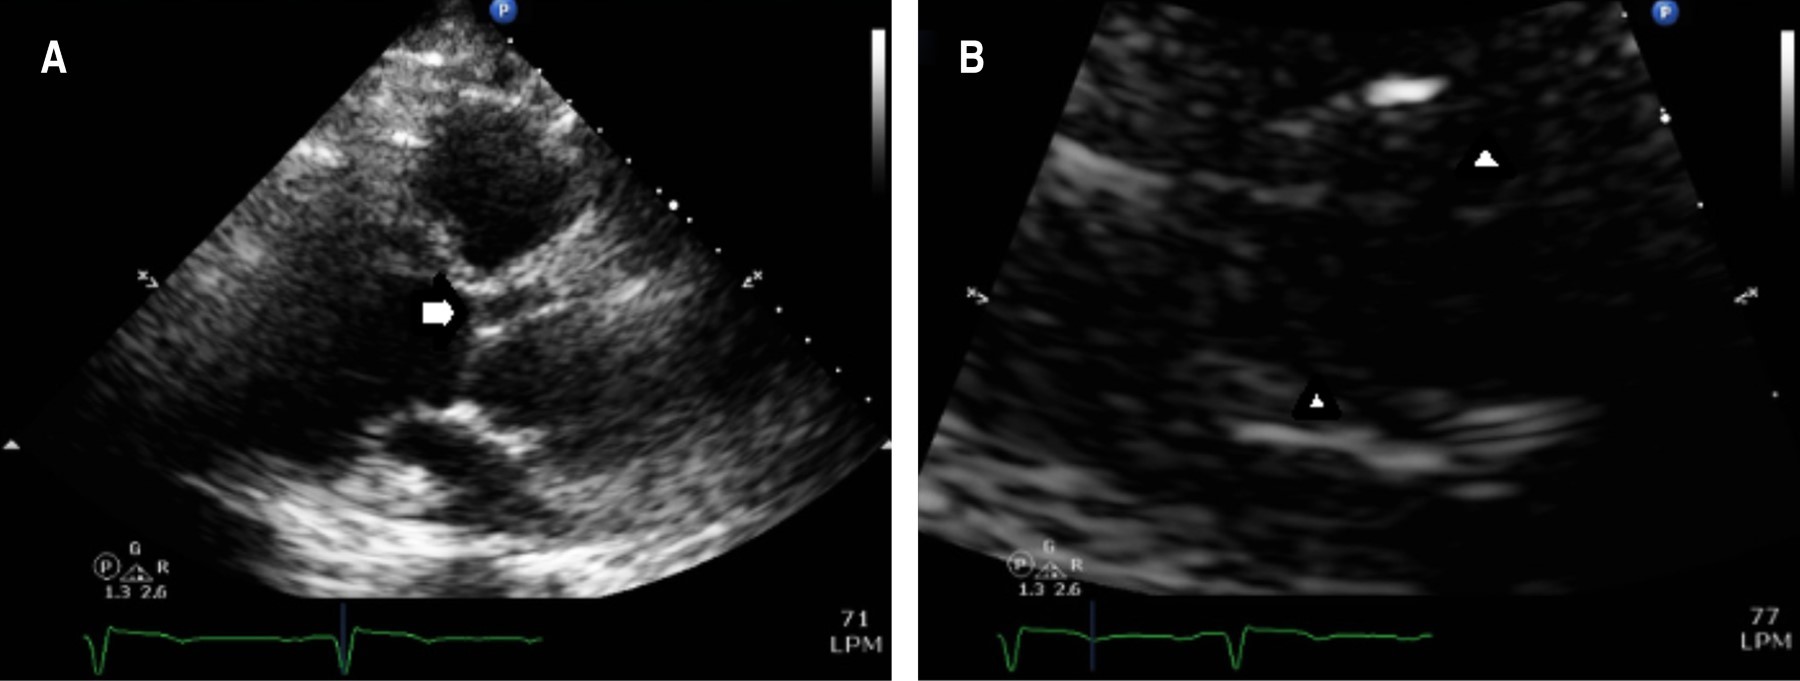

Coartación aórtica asociada a válvula aórtica bicúspide complicada con aneurisma aórtico postdisección

Sánchez-Amaya DJ, Godínez-Córdova LB, López-Lizárraga MÁ, Araiza-Garaygordobil D, Arias-Mendoza A

coartación aórtica, disección aórtica crónica, aneurisma aorta ascendente, válvula aórtica bicúspide.

La coartación aórtica es un trastorno congénito que afecta no solamente a la aorta, sino que también puede asociarse a válvula aórtica bicúspide y predispone a síndromes aórticos. Se reporta el caso de un paciente de 28 años de edad con hipertensión secundaria debido a coartación aórtica postductal asociada a válvula aórtica bicúspide que a su vez presentó disección crónica de la aorta ascendente. La coexistencia de enfermedad valvular aórtica, así como múltiples condiciones aórticas, es una situación rara que requiere una evaluación altamente especializada para garantizar un resultado favorable. El tratamiento se estableció en dos fases: aortoplastia con colocación de stent y luego cirugía de reemplazo aórtico y valvular, con una recuperación favorable.

Figura 2